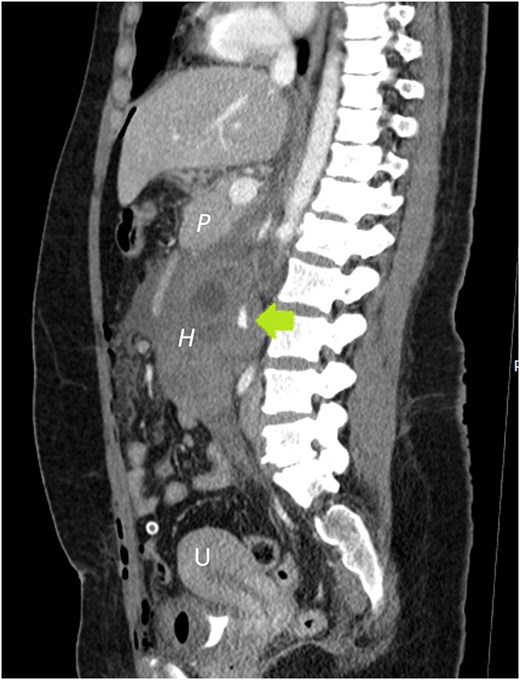

She underwent abdominal sonography followed by contrast-enhanced computed tomography (CECT). Both demonstrated a right-sided retroperitoneal hematoma adjacent to the inferior vena cava and right kidney. A 5 cm ring-shaped structure resembling an empty gestational sac was detected inside the hematoma (Fig. 1). CT showed contrast extravasation representing active bleeding (Figs 2 and 3). Interdisciplinary team discussion, including obstetrician-gynecologists, abdominal surgeons, anesthesiologists, and radiologists, led to the decision for emergency relaparotomy.

Sagittal plane CECT shows the hematoma (H) displacing the pancreas ventrally, proving its retroperitoneal location. Active bleeding is seen adjacent to the gestational sac (arrow). A normal appearing, nonpregnant uterus is also visible.